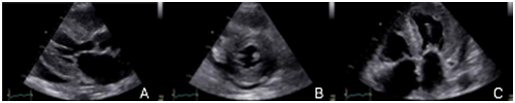

Figure 1 We can see a parasternal long axis view (A), short axis at mid ventricular level (B) and 4 chambers (C), showing mild hypertrophy (12mm) with biatrial enlargement and mild pericardial effusion (White arrow).

Subsequently, she was admitted to our institution with a clinic diagnosis of acute heart failure, Stevenson B. A chest X-ray showed bilateral pleural effusion, grade II. During the admission, the only significant finding was mild anemia (Hb 11,1g/dl). A transthoracic echocardiogram (Figure 1 & Video 1) was done showing normal left ventricle diameters, LV ejection fraction 47%, mild concentric hypertrophy, biatrial enlargement, mild to moderate mitral regurgitation, pseudo normal ventricular filling pattern, e 4cm/sec, E/e´ ratio greater than 18, moderate tricuspid insufficiency, an estimate pulmonary artery systolic pressure of 55mmHg and mild pericardial effusion. The presumptive diagnosis of infiltrative restrictive cardiomyopathy was assumed. A myocardial 3D strain imaging with speckle tracking was done, showing normal longitudinal strain of apical segments and a strong impaired values of basal and mid segments (-16 to -28 at apical segments vs 4 to -4 at basal level) (Figure 2C). The patient improved clinically with diuretics and vasodilators according to local guidelines. Nevertheless, during the third day of hospitalization she experiences a sudden death episode, with ventricular tachycardia documented in the telemetric system, with an adequate response to cardiopulmonary resuscitation (CPR).